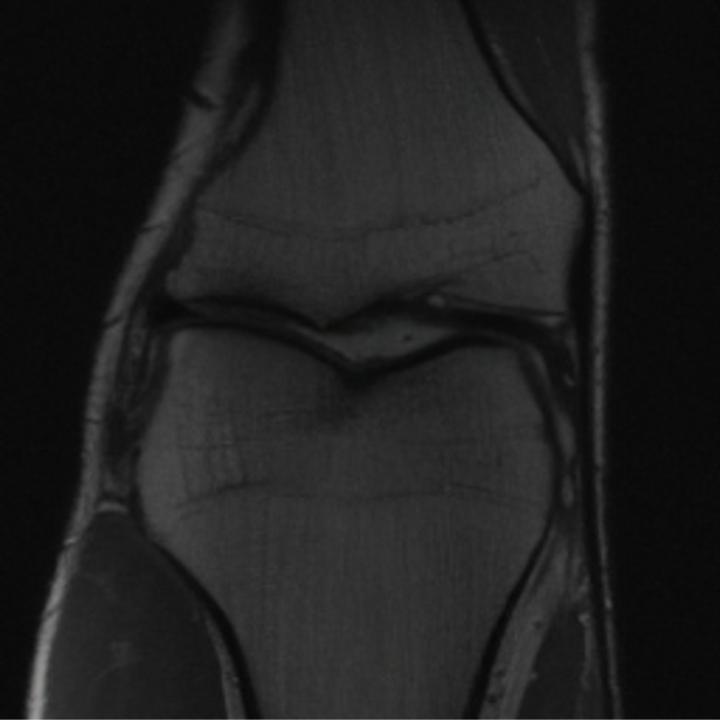

One way to test the generalization capability of the trained X-Diffusion is to test it on a completely different domain from an MRI dataset not seen during training. We report the single-slice results on the test set of knees from NYU fastMRI [33, 80], using the X-Diffusion trained on the BRATS brain MRIs. The test PSNR result is 34.17 and an example is shown in Figure 8. It shows how successfully X-Diffusion can generate knee MRIs (out-of-domain) despite being trained on brains.

Small Knee MRIs clinical study. To qualitatively assess how realistic our generated knee out-of-domain 3D volumes were (produced from a single slice), we gave 20 generated examples alongside their real MRI counterparts to an expert orthopedic surgeon J. F.. He was then asked to identify the real example from a set of 20 MRI pairs. The surgeon correctly identified the real MRI in only 10 out of 20 pairs, could not decide in 3 pairs, and misidentified the generated MRI as real in the remaining 7 pairs. This further validates the generated out-of-domain MRIs.